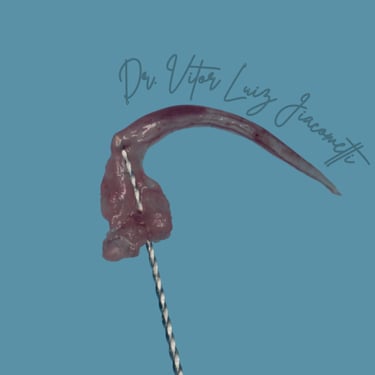

Implante sem corte ou bisturi já é uma realidade

É possível planejar e fazer implantes dentários sem a necessidade de cortes ou bisturis. Utilizando a tecnologia digital, o procedimento se torna mais preciso e menos invasivo.

O planejamento é feito em um computador com base em tomografias e escaneamentos da boca do paciente. Com esses dados, um guia cirúrgico é impresso em 3D. Esse guia se encaixa na boca do paciente e mostra o local e o ângulo exatos para a inserção do implante, evitando a necessidade de abrir a gengiva com bisturi.

A cirurgia é mais rápida, tem um pós-operatório mais tranquilo e com menos inchaço e dor. A recuperação também costuma ser mais rápida, e o resultado final é mais estético.

Planejamento digital do implante

O planejamento digital permite fazer a cirurgia sem bisturi e em poucos minutos.